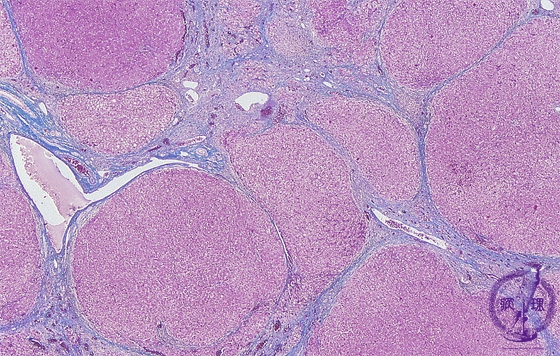

- 10.Liver

- ★(1)Viral hepatitis, cirrhosis

Microscopic image (AZAN trichrome stain, low power): Liver cirrhosis due to chronic hepatitis. There is a loss of lobular architecture with effacement of normal parenchyma by regenerative hepatocellular nodules of various sizes. Narrow fibrous septa surround and separate regenerative nodule.

Click the image to see the enlarged image.